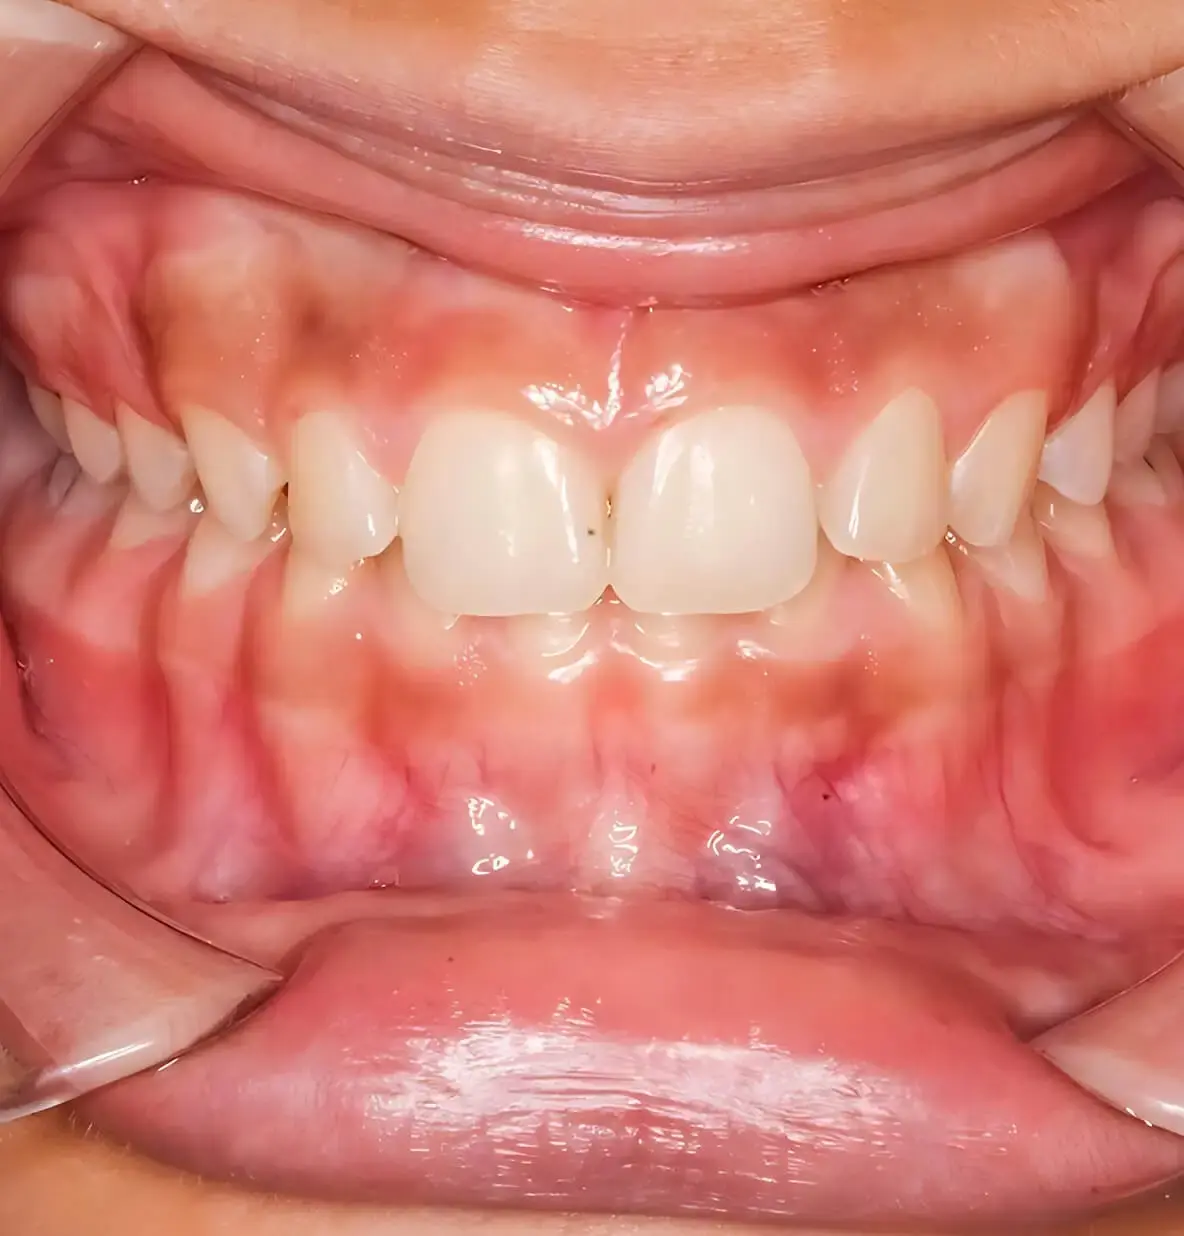

Глубокий прикус зубов — аномалия, при которой верхние резцы слишком (более чем на 1/3) перекрывают нижние при смыкании челюстей. В тяжелых случаях нижние зубы могут упираться в небо, травмируя слизистую оболочку и вызывая постоянный дискомфорт.

Симптомы глубокого прикуса у взрослых и детей видны при внешнем осмотре лица и в полости рта: укорочение нижней трети лица. Глубокое перекрытие, когда нижние резцы более чем наполовину скрыты под верхними. На внутренней стороне верхних зубов или десне нижних зубов снаружи видны следы от прикусывания. Изменение расположения подбородка из-за наличия дистальной или мезиальной окклюзии в сочетании с глубоким перекрытием. Выраженная надподбородочная складка.

глубокий прикус